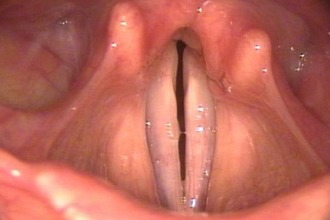

Ларингит — это воспалительное заболевание, поражающее слизистую оболочку гортани. Инфекционные формы ларингита могут быть вызваны бактериями, вирусами и грибами. Гортань, часть дыхательной системы, обеспечивает свободное прохождение воздуха в нижние дыхательные пути. При инфекционно-воспалительном процессе может возникнуть обструкция (закрытие просвета) из-за отека, давления воспалительного инфильтрата или накопления патологических образований. Это приводит к остановке воздушного потока и, как следствие, к удушью (асфиксии).

Существует множество видов инфекционных ларингитов, но не все они вызывают нарушения дыхания. Важным фактором являются анатомические особенности, особенно у детей, у которых просвет гортани узкий, что увеличивает риск его частичного или полного закрытия. Рассмотрим несколько значимых вариантов воспаления гортани, влияющих на дыхательные функции: